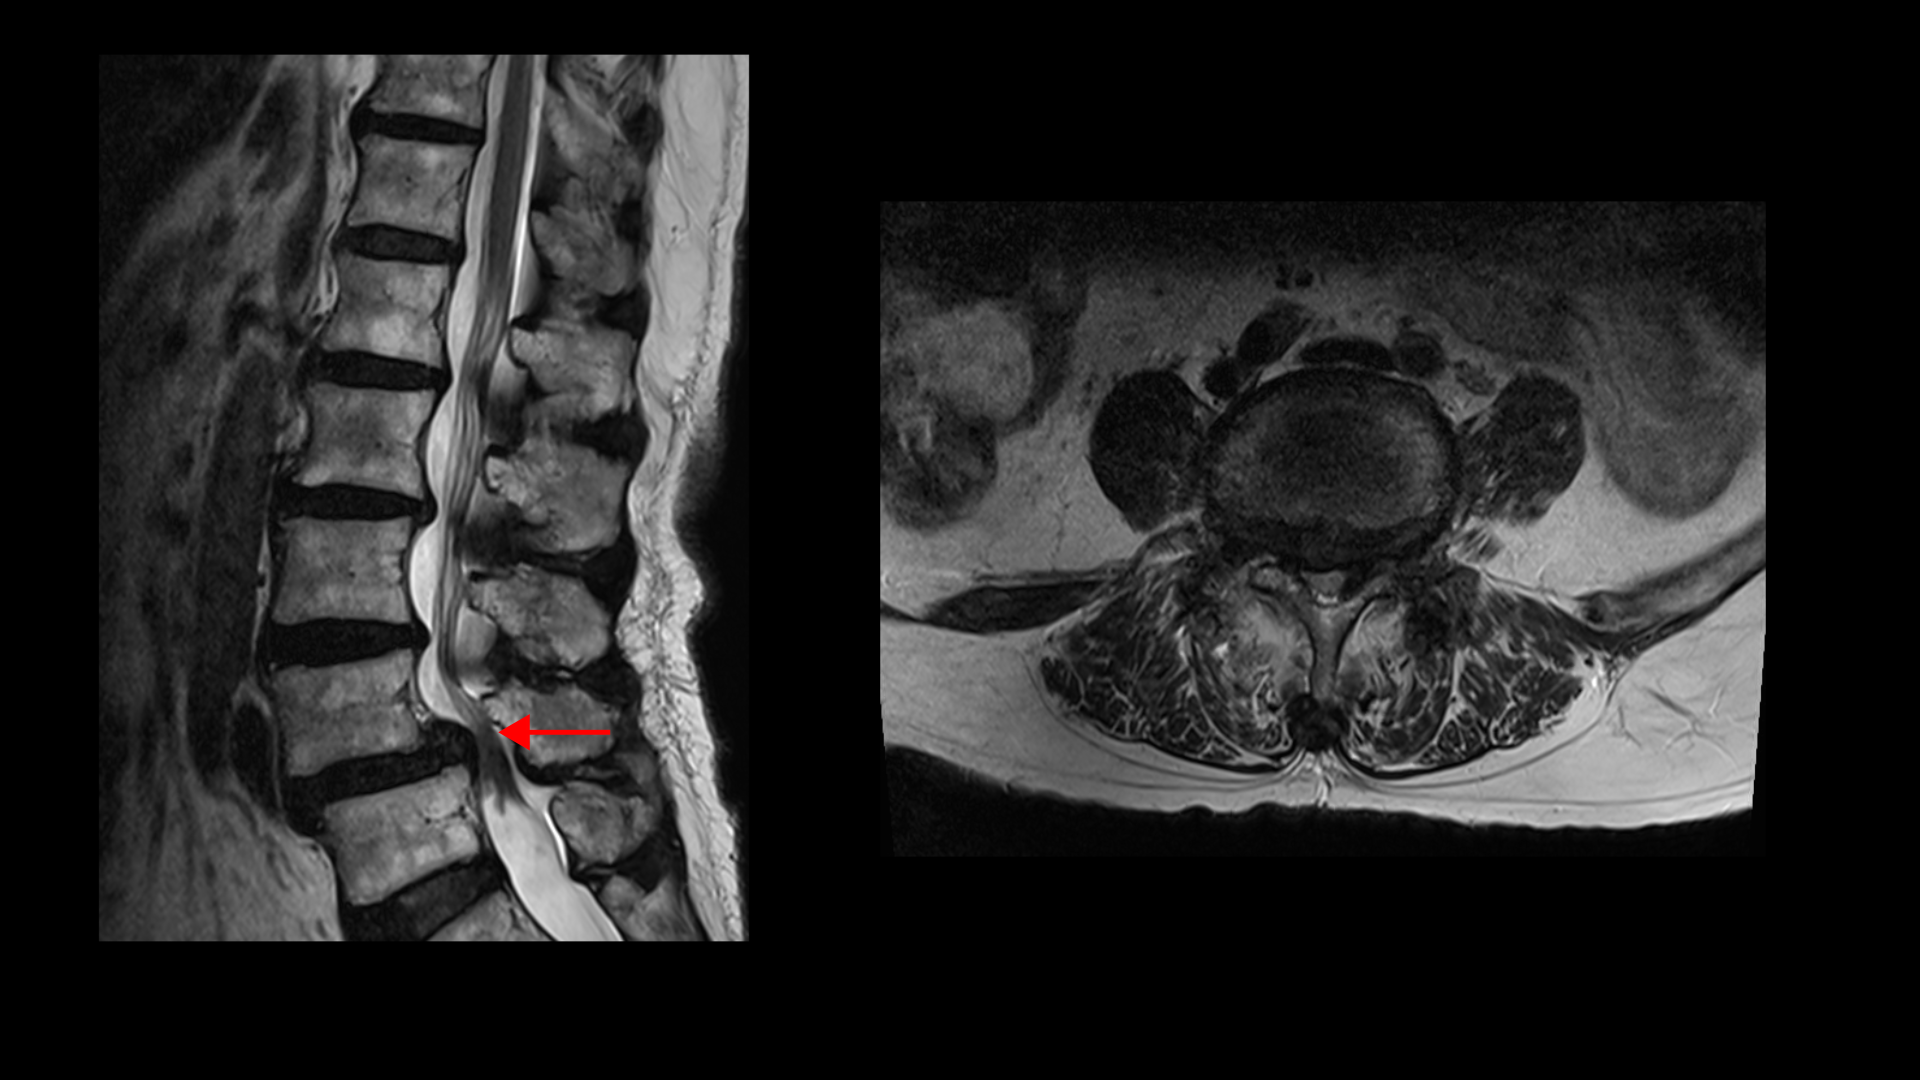

이 환자분의 근육을 MRI에서 보면 5번, 1번 마디에서 기립근과 장요근을 체크해봤을 때 기립근의 지방화 정도도 심하고 장요근, 특히 왼쪽 장요근은 거의 형체를 알아보기 어려울 정도로 위축이 심한 상태입니다.